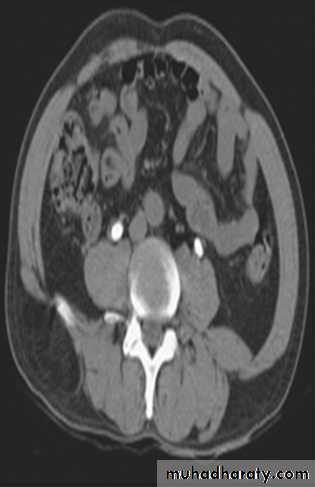

RENAL CELL CARCINOMA(RCC)

Most common malignant renal masses.Spherical or lobulated similar density to the adjacent renal cortex.

May have areas of necrosis.

Enhances heterogeneously and less than that of the adjacent renal parenchyma.

CT is sufficiently accurate so that preoperative biopsy is rarely performed.

Staging is best by CT except for vascular invasion where MRI will be superior.

Staging parameters include : local direct spread, retroperitoneal L.Ns enlargement, liver adrenal or pancreatic metastasis and renal vein or IVC involvement.